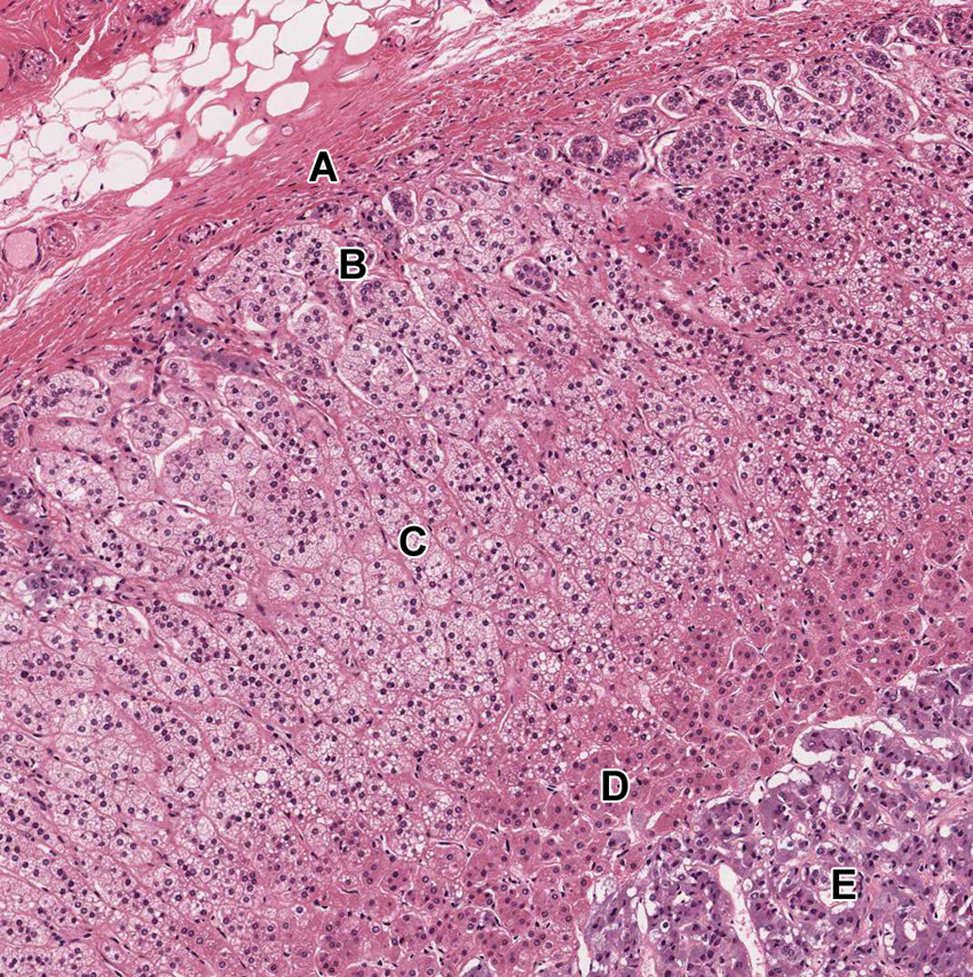

One possible cause of adrenal hyperplasia (hyperactivity) may be over-proliferation (e.g. a tumor) of which PITUITARY cell type indicated in this trichrome-stained section?

A. A

B. B

C. C

D. D

A

The zones of the adrenal gland are labeled in the attached image. Which zone synthesizes the largest amount of mineralocorticoids (such as aldosterone)?

A. A

B. B

C. C

D. D

E. E

B.B

Acromegaly leading to gigantism is caused by the excessive secretion of hormone from which of the following labeled cells?

A. A

B. B

C. C

D. D

C. C

The zones of the adrenal gland are labeled in the attached image. Overactivity of cells in which zone would cause virilization within women?

A. A

B.B

C. C

D.D

E.E

D. D